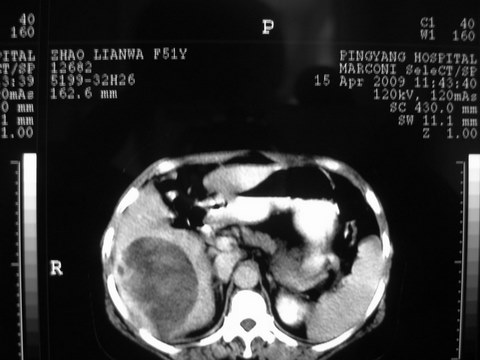

患者 女 51岁 两天前感觉上腹疼,无明显诱因,b超示肝右叶囊实性占位,边缘清楚,其内回声不均匀,ct增强如图,大家看看是什么 ,病人一年前及两月前b超检查只是提示胆囊炎

外院术后,证实肝癌合并出血

出病理 中分化肝细胞癌合并出血